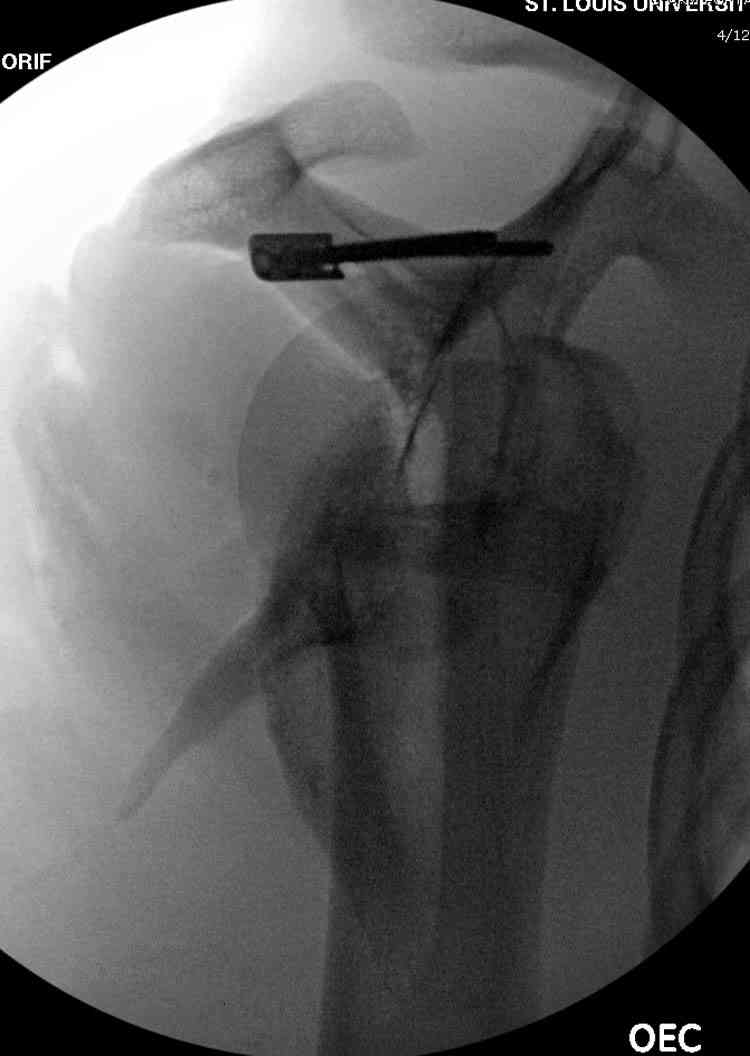

На снимке (№6 компьютерная томограмма и 3D №7) перелом клювовидного отростка.

Передним дельтопекторальным Bankart доступом намного легче провести фиксация отростка, но тогда репозиция и фиксация колонн затрудняется, поэтому был применен стандартный Judet задний доступ.

Репозицию смогли сделать пальцами через щель между

шейкой и телом лопатки (последний 3D снимок)

Двумя шурупами сзади на пластине (вместе шайбы)

провели удержание репозиции, а фиксацию провели

следующим косым шурупом.

Последующие этапы на снимках.

Планирую через четыре недели сделать рентген-контроль с решением вопроса об удалении АВФ. Аппарат смонтирован из деталей аппарата Илизарова. Картинки в приложении.